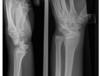

two significant findings

what are the management priorities?

A

• grossly deformed swollen left wrist consistent with distal radial +/- ulna fracture

• dorsal angulation distal radius

• skin breech and bleeding

**Management **

1. analgesia

2. assess for nerve damage

3. ‘urgent reducion

4. iv abx

5. tetanus

6. POP and post reducion imaging

7. ortho referral

wrist pain - what are the relevant findings? short and long term complications of this injury?

peri lunate dislocation scaphoid fracture short term complications: * median nerve injury * pressure necrosis of skin * compartment syndrome * pain * loss of function Long term complications * avascular necrosis scaphoid * carpal instability * chronic pain * OA

73

9 year old FOOSH describe abnormalitis

salter harris 1 distal radius dorsal angulation dorsal displacement epiphysis

74

abnormalities

terry thomas sign - scapholunate dislocation radial and ulna styloid fracture